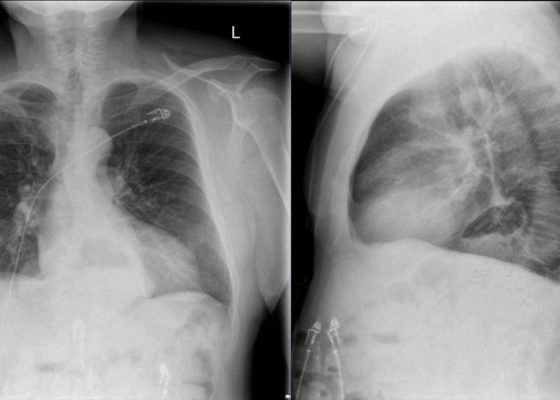

Incidental Hiatal Hernia on Chest X-ray

DOI: https://doi.org/10.21980/J8KP8SThe two-view chest X-ray shows mild opacification of the bilateral lower lobes concerning for pneumonia (red arrows). Incidental retrocardiac opacity with air-fluid level consistent with large hiatal hernia is also observed (green arrow).